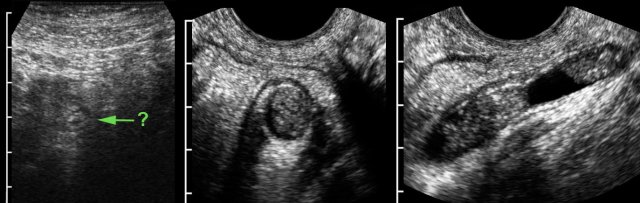

TVUS detects inflamed appendix in deep pelvic location. TVUS detects inflamed appendix in deep pelvic location.

In this obese, 3 weeks pregnant woman, transabdominal US visualized an dubiously abnormal appendix (← ?).

TVUS showed a dilated, pus filled, inflamed appendix in deep pelvic location.